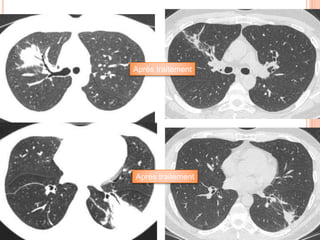

Patiente 52 ans, toux

trainante, asthénie, apyrexie

Il y a quelques semaines,

monoplégie du bras gauche

au réveil, ayant régressé

totalement

Biopsies bronchiques: sur un

des fragments, possible

micro abcès à polynucléaires

neutrophiles au voisinage de

capillaires

Après traitement